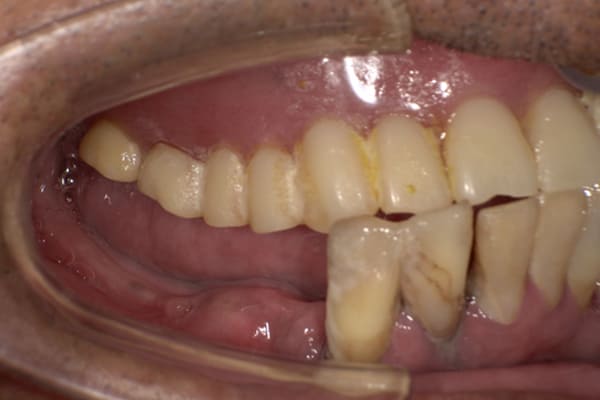

歯周病により歯はぐらぐらで歯茎は腫れた状態です。かみ合わせも、もともと受け口で下の歯が前にでているのが分かります。

治療後は、入れ歯により受け口も治し正常のお口元に。

治療前は上の入れ歯の歯のラインが湾曲し、下の歯が前に出ているのが分かります。

治療後は、歯のラインが真っすぐとなり、下の歯も正常のかみ合わせになっています。